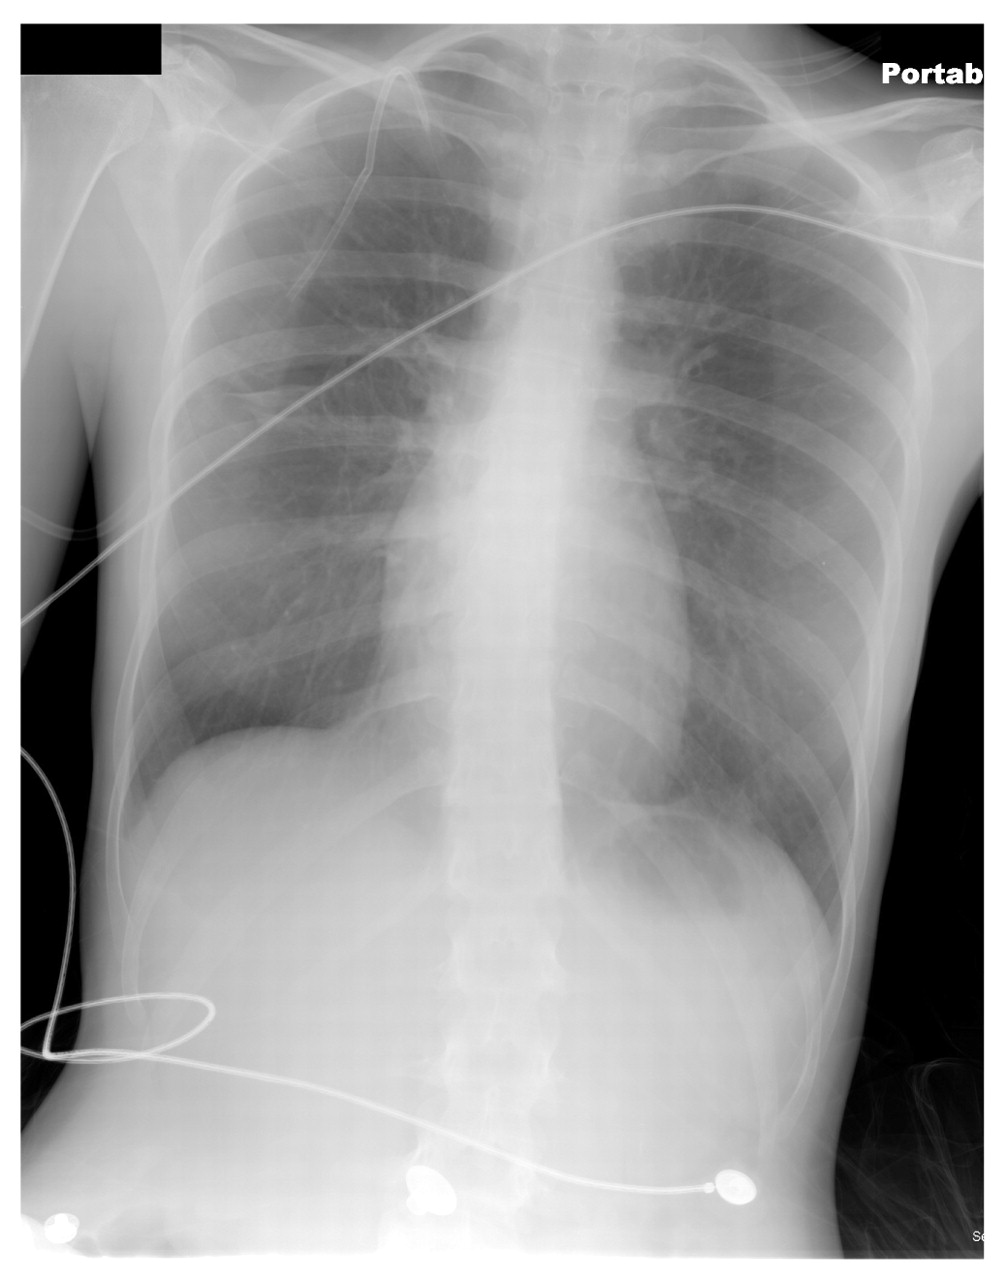

Postprocedure radiographic evidence demonstrated complete reexpansion of the right lung with the catheter in the appropriate position (Figure 2). The patient tolerated the procedure well and was admitted to the hospital for observation. Complete resolution of the pneumothorax was observed, and the catheter was removed. The patient was discharged on hospital day 3 in good condition. Both the patient and her boyfriend were educated regarding the dangers of the home remedy they used. They were encouraged to refrain from future self-treatments.

Postprocedure chest radiograph of a 20-year-old woman who required a chest tube thoracostomy and hospitalization as a result of a pneumothorax. This radiographic image demonstrates the complete reexpansion of the patient's right lung with the catheter appropriately positioned.